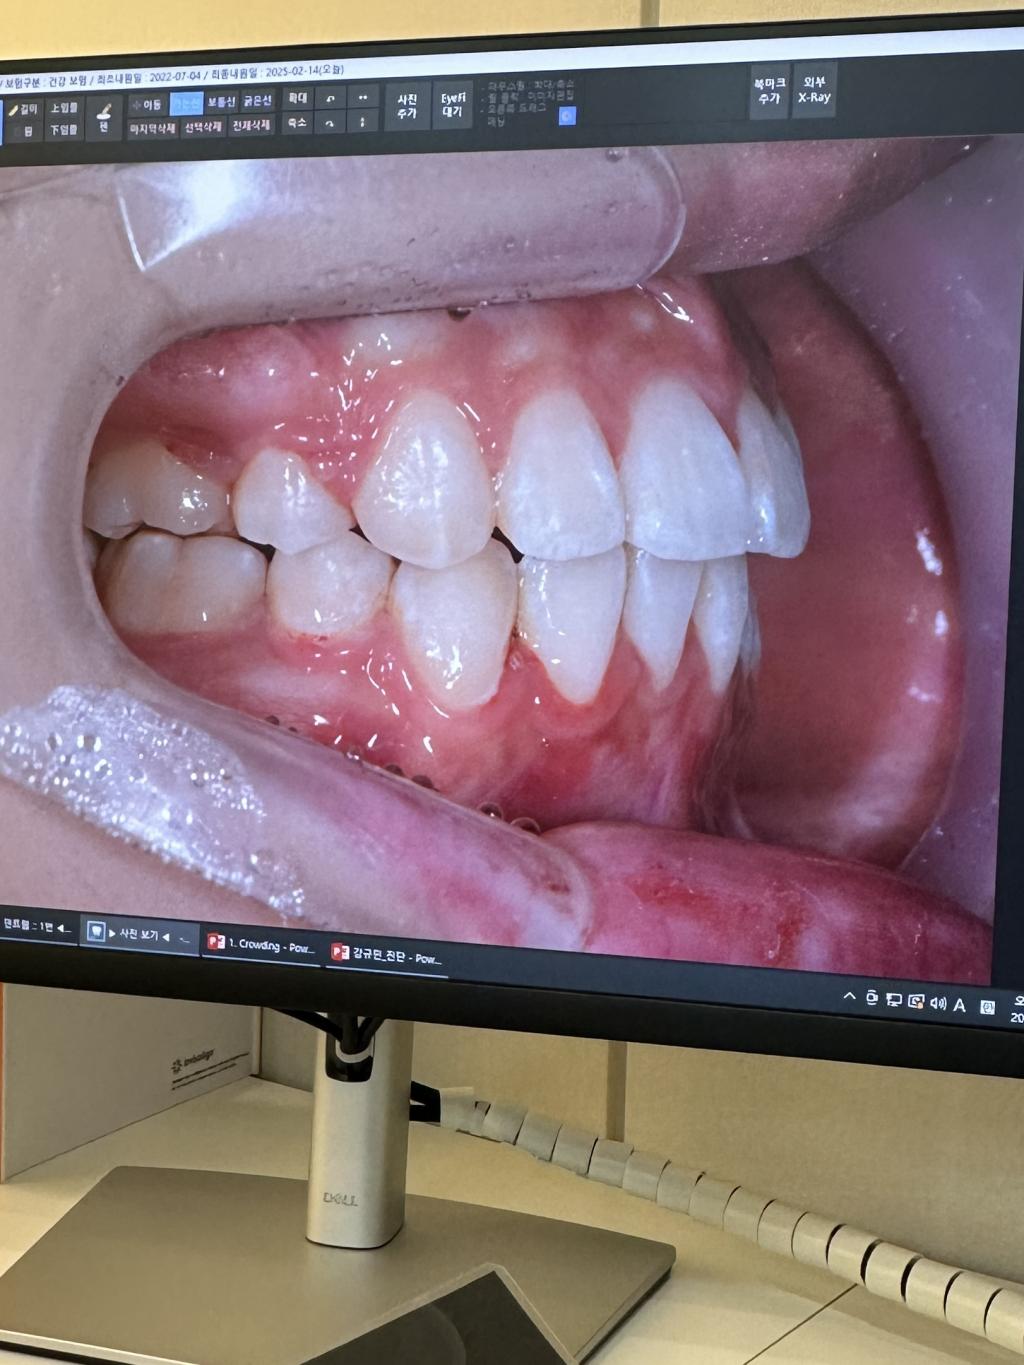

완료된 사진입니다,, 앞니가 덜 넣은게 맞는거죠.. 더 넣고싶어요..

보내주신 사진을 보니 위 아래 앞니 사이에 공간이 있습니다. 이런 경우에 쉽게 가는 방법은 위 앞니 사이를 약간씩 삭제하고 가철식 유지장치를 이용해서 위 앞니들을 뒤로 조금 이동시키고 나서 고정식 유지장치를 다시 만드는 것입니다.

그렇지 않은 경우는 위 전체 치아에 고정식 교정장치를 다시 붙여서 위턱 잇몸 뼈에 스크류를 심어서 전체 치아를 뒤로 이동시키는 방법이 있습니다. 그러니 이 경우는 어금니의 교합이 약간 틀어질 수가 있습니다.

마무리로, 위에 설명 드린 방법들이 있는데 저라면 위 잎니의 각도를 줄이기 만을 원하신다면 첫 번째 방법으로 가는 것을 추천드립니다.